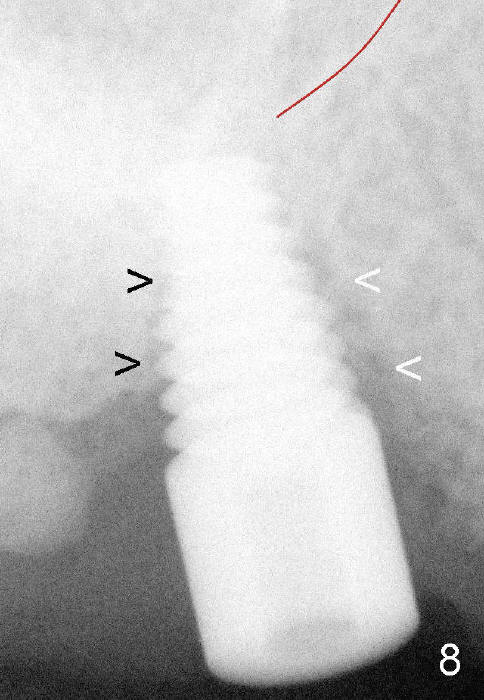

Fig.8: A 6x14 mm tapered implant is placed with insertion torque >60 Ncm. The implant almost obliterates the extraction socket (<) and is close to the sinus floor (red line).